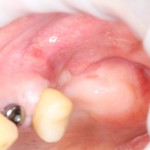

Имплантация и остеопластика: вместе или врозь? Часть II плюс Ankylos, плюс Geistlich